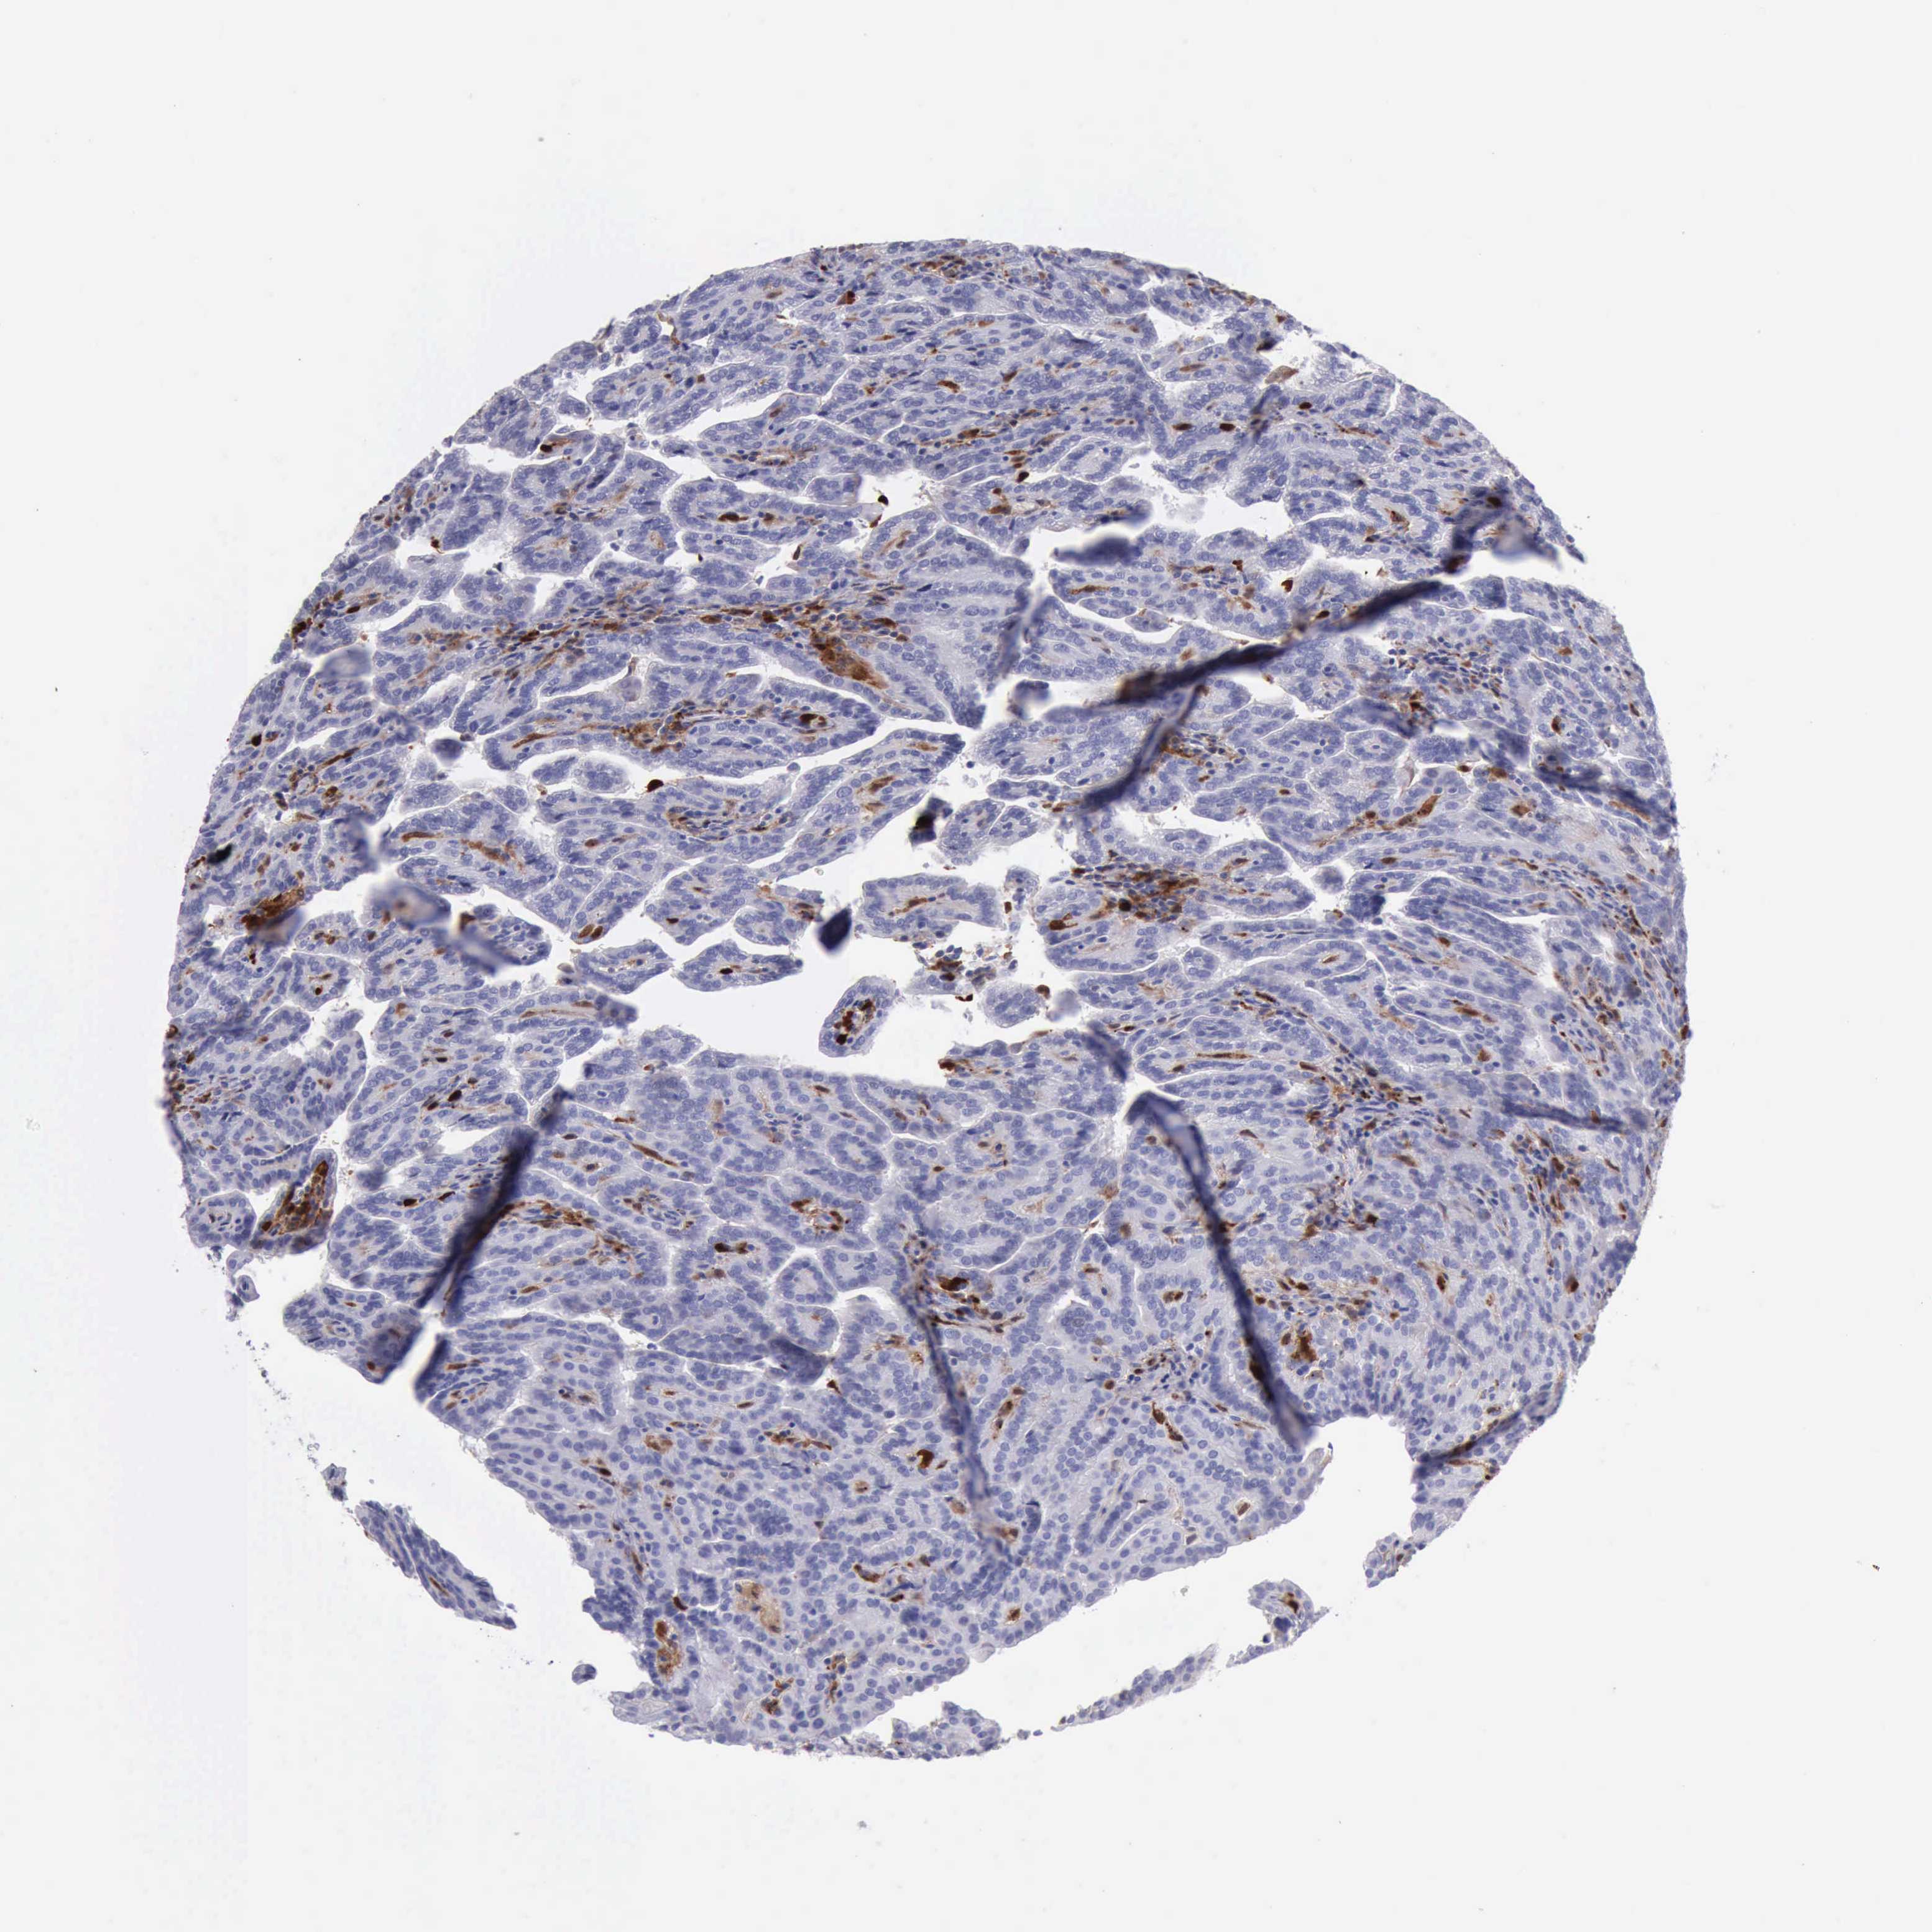

KIDNEY RENAL CLEAR CELL CARCINOMA (VALIDATION) - Interactive survival scatter ploti

The Survival Scatter plot shows the clinical status (i.e. dead or alive) for all individuals in the patient cohort, based on the same data that underlies the corresponding Kaplan-Meier plots. Patients that are alive at last time for follow-up are shown in blue and patients who have died during the study are shown in red.

The x-axis shows the expression levels (FPKM) of the investigated gene in the tumor tissue at the time of diagnosis. The y-axis shows the follow-up time after diagnosis (years). Both axes are complimented with kernel density curves demonstrating the data density over the axes. The top density plot shows the expression levels (FPKM) distribution among dead (red) and alive patients (blue). The right density plot shows the data density of the survived years of dead patients with high and low expression levels respectively, stratified using the cutoff indicated by the vertical dashed line through the Survival Scatter plot. This cutoff is automatically defined based on the FPKM cutoff that minimizes the p-score. The cutoff can be changed by dragging the vertical line or by entering a cutoff value in the square labeled "Current cut-off".

Under the Survival Scatter plot the p-score landscape (black curve; left axis) is shown together with dead median separation (red curve; right axis). Dead median separation is the difference in median mRNA expression between patients who have died with high and low expression, respectively. It is calculated as follows: median FPKM expression of dead patients with high expression - median FPKM expression of dead patients with low expression. This is intended to aid the user in visually exploring custom cutoffs and the associated p-scores and dead median separation.

Individual patient data is displayed and can be filtered by clicking on one or more of the category buttons on the top of the page. Categories describing expression level and patient information include: high, low, alive, dead, female, male and tumor stages. The scale of the x-axis can be toggled between linear and log-scale by clicking on the "x log" button. Mouse-over function shows TCGA ID, patient information and mRNA expression (FPKM) for each patient.

& Survival analysisi

Kaplan-Meier plots summarize results from analysis of correlation between mRNA expression level and patient survival. Patients were divided based on level of expression into one of the two groups "low" (under cut off) or "high" (over cut off). X-axis shows time for survival (years) and y-axis shows the probability of survival, where 1.0 corresponds to 100 percent.

CSTA is not prognostic in Kidney Renal Clear Cell Carcinoma (validation)

Best expression cut offi

Based on the FPKM value of each gene, patients were classified into two groups and association between prognosis (survival) and gene expression (FPKM) was examined. The best expression cut-off refers the FPKM value that yields maximal difference with regard to survival between the two groups at the lowest log-rank P-value. Best expression cut-off was selected based on survival analysis .

When clicking on this number, the vertical dashed line indicating cut-off, the interactive survival plot, and the Kaplan-Meier curve will be adjusted to show results based on the best expression cut-off.

: 19.04

Median expressioni

Median expression refers to the median FPKM value calculated based on the gene expression (FPKM) data from all patients in this dataset. When clicking on this number, the vertical dashed line indicating cut-off, the interactive survival plot, and the Kaplan-Meier curve will be adjusted to show results based on the median expression.

: N/A

Median follow up timei

Median follow up time refers to the median time (years) after diagnosis with this type of cancer, based on clinical data from all patients in this dataset.

P scorei

Log-rank P value for Kaplan-Meier plot showing results from analysis of correlation between mRNA expression level and patient survival.

N/A

5-year survival highi

5-year survival for patients with higher expression than the expression cutoff.

For melanoma and glioma, 3-year survival is shown.

5-year survival lowi

5-year survival for patients with lower expression than the expression cutoff.

TCGA RNA samplesi

RNA-seq data is reported as average FPKM (number Fragments Per Kilobase of exon per Million reads), generated by the The Cancer Genome Atlas (TCGA) .

Normal distribution across the dataset is visualized with box plots, shown as median and 25th and 75th percentiles. Points are displayed as outliers if they are above or below 1.5 times the interquartile range. FPKM values of the individual samples are presented next to the box plot.

Average pTPM 15.1

Number of samples 100